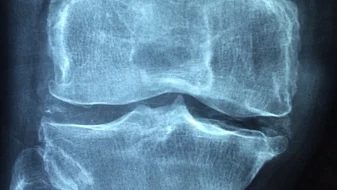

髋关节退行性变的诊断需要详细的病史和体格检查。临床上典型表现为髋部疼痛、僵硬和活动受限。X线片是诊断髋关节退行性变的首选影像学检查,可以显示关节间隙变窄、软骨下骨硬化、骨赘形成等改变,必要时可结合磁共振成像(MRI)以评估软组织和关节软骨的状况。

髋关节退行性变的分期主要依据临床症状和X线影像学表现。根据Kellgren和Lawrence(K&L)分级标准,髋关节退行性变分为五级:0级为无变化,I级为疑似变化(可能有间隙变窄和骨赘形成),II级为轻度(明确的小骨赘和轻度间隙变窄),III级为中度(中等大小的骨赘和显著间隙变窄),IV级为重度(大骨赘、严重的间隙变窄或关节间隙完全消失)。这一标准结合患者临床表现,能基本满足临床需求。